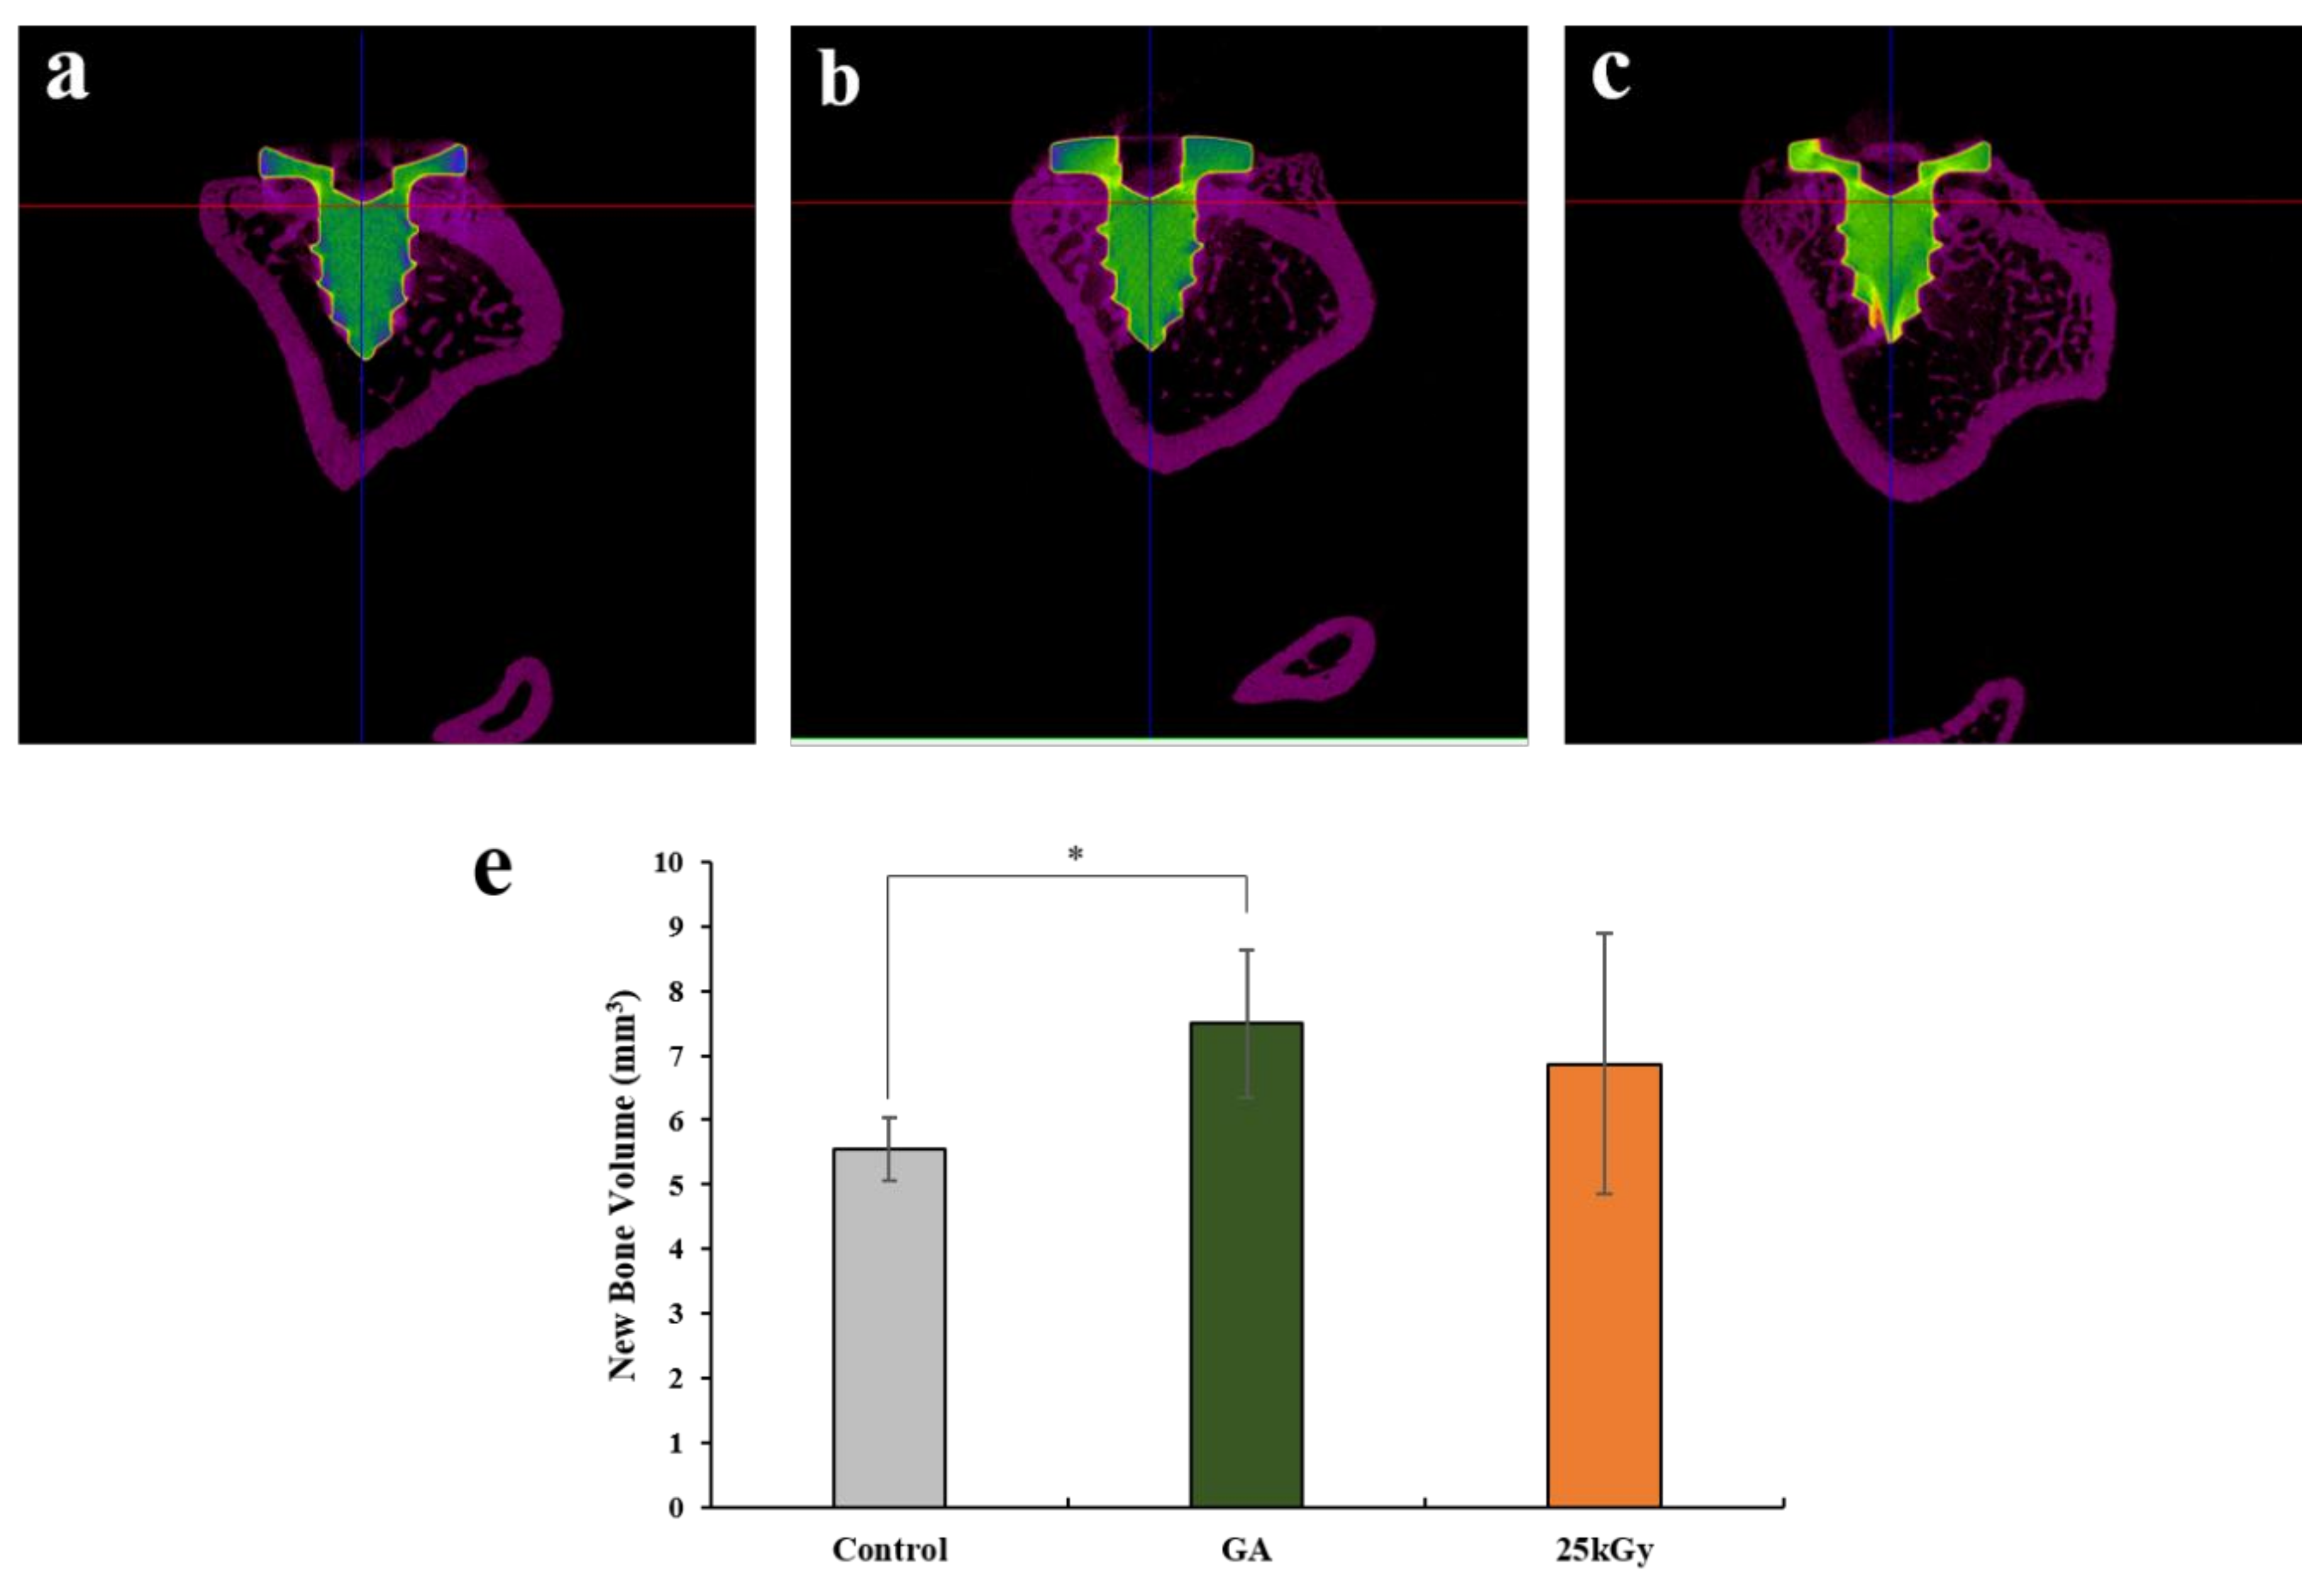

2.2.2. Micro-Computed Tomography (μCT) Findings

4.3.3. Micro-Computed Tomography (μCT) Analysis

| Group | Mean ± SD | Median |

|---|---|---|

| Control | 5.55 ± 0.48 | 5.55 |

| GA | 7.50 ± 1.14 | 7.81 |

| 25 kGy | 6.87 ± 2.01 | 7.47 |

| p-value | 0.006 ** | |